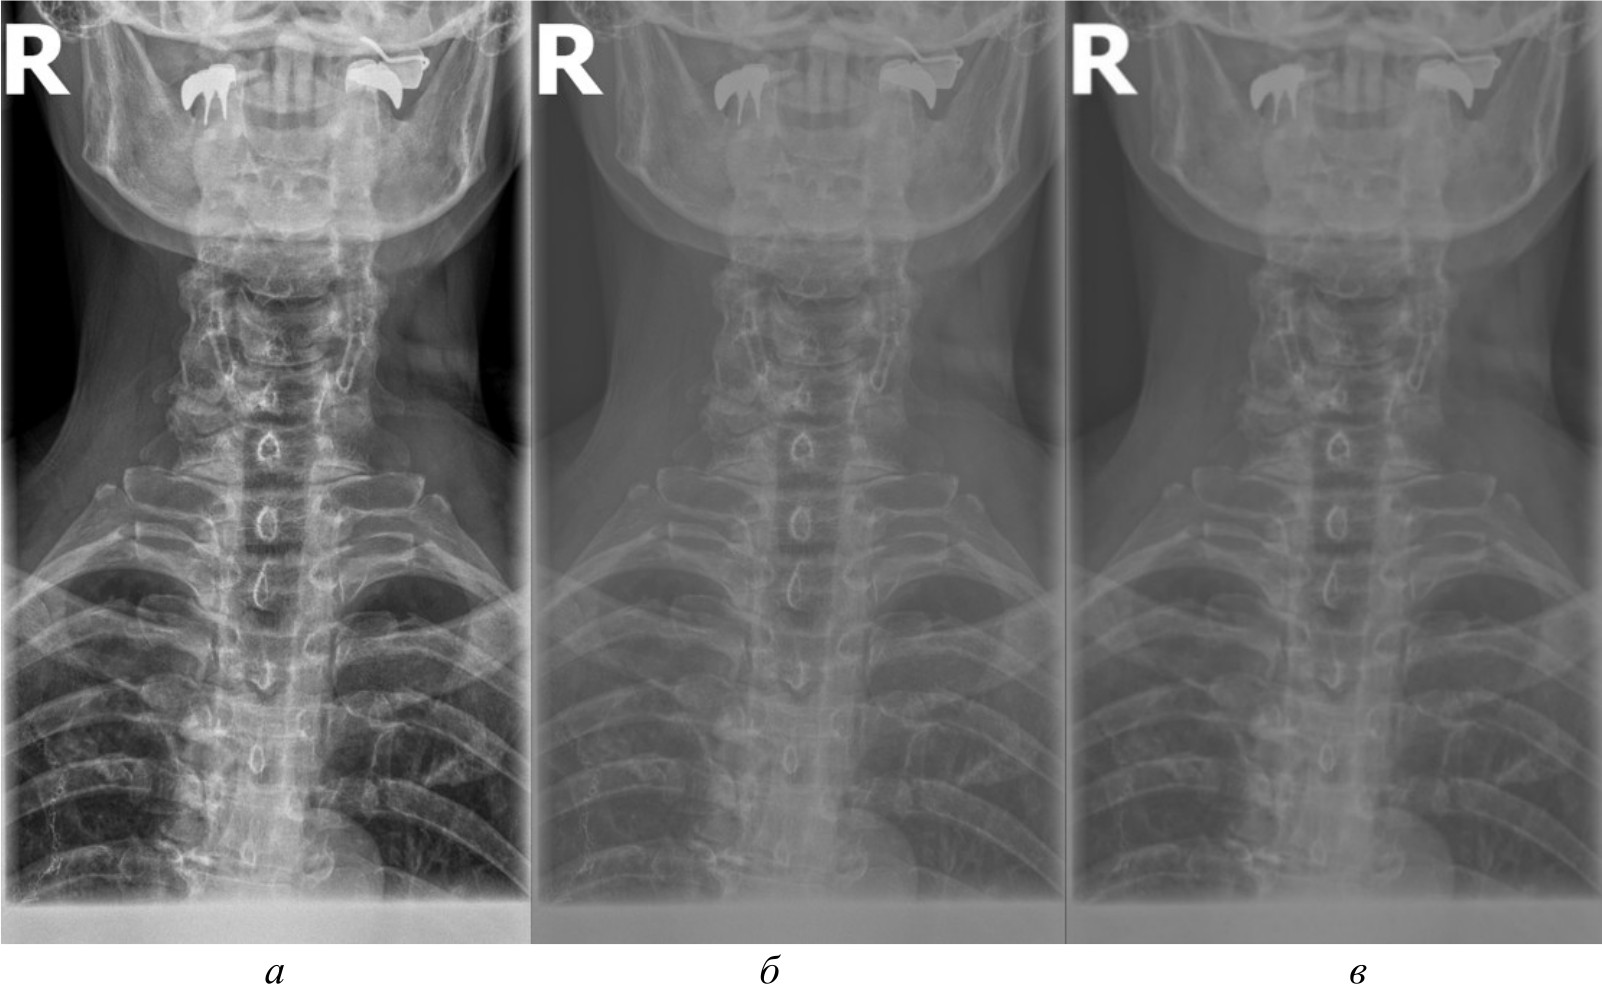

Для создания эталонного набора изображений рентгеновские снимки в формате DICOM были загружены в специализированное программное обеспечение для медицинской визуализации. DICOM является стандартным форматом для медицинских изображений, который позволяет сохранять изображение с высоким качеством и дополнительной информацией об исследовании. Однако для дальнейшей обработки и анализа эти DICOM-файлы конвертируются в более распространенные графические форматы. Специализированное программное обеспечение сохраняет их в формате PNG. На рис. 2, а представлено изображение, полученное в результате работы в специализированном программном обеспечении.

Несмотря на то, что PNG является одним из четких графических форматов, он все же может приводить к некоторой потере качества по сравнению с исходными DICOM-файлами. Поэтому для извлечения более качественных изображений и проведения более детального анализа применяются алгоритмы и методы компьютерного зрения, которые способны работать непосредственно с DICOM-данными, избегая потерь при конвертации.

Для сравнительного анализа использовались различные методы и алгоритмы компьютерного зрения. Помимо изображений в формате PNG, конвертированных из исходных DICOM-файлов, применялись и другие подходы, направленные на извлечение более качественных изображений непосредственно из DICOM-данных, среди которых:

- базовое отображение Python. Изображения загружены в Python и отображены при помощи библиотеки Pillow без применения каких-либо дополнительных преобразований. Данный метод представлен на рис. 2, б;

- медианный фильтр. Для сглаживания шумов и артефактов на изображениях к базовому отображению Python применен медианный фильтр из библиотеки OpenCV. Размер окна фильтра был подобран эмпирически. Данный метод обработки представлен на рис. 2, в;

Рис. 2. Изображение, полученное при помощи специализированного программного обеспечения (а), метод базового отображения в Python (б), метод базового отображения Python с применением медианного фильтра (в)

Исходя из полученных изображений при использовании различных методов можно сделать следующие выводы:

- базовое отображение DICOM-данных с помощью библиотеки Pillow показало наличие значительного количества шумов и размытых объектов на полученных изображениях, что затрудняет четкое обнаружение анатомических ориентиров;

- применение медианного фильтра для сглаживания артефактов привело к чрезмерному размытию деталей на изображениях, сделав их еще менее пригодными для дальнейшего анализа;

- использование методов эквализации гистограммы продемонстрировало значительное улучшение контрастности и четкости визуализации анатомических структур по сравнению с базовым отображением и медианной фильтрацией;

- гамма-коррекция изображений, в отличие от эквализации, больше повлияла на яркость, нежели на контрастность, поэтому показала себя хуже в контексте задачи выделения ключевых анатомических ориентиров;

- отображение изображений в формате PNG, полученных из исходных DICOM-данных после применения ряда предварительных обработок с помощью специализированного программного обеспечения, продемонстрировало качество визуализации несколько меньшее, чем у методов эквализации, но при этом превосходящее качество других рассматриваемых методов обработки. В итоге комплекс предварительных обработок, необходимых для конвертации DICOM-данных в формат PNG, позволяет достичь качества визуализации, которое хотя и уступает эквализации, но превосходит другие методы.